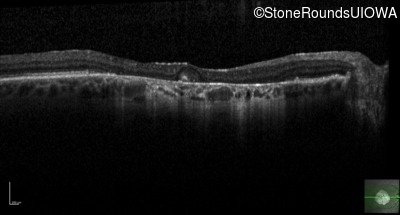

Optical Coherence Tomography - Right - 20/125

Exemplar / OCT Stack